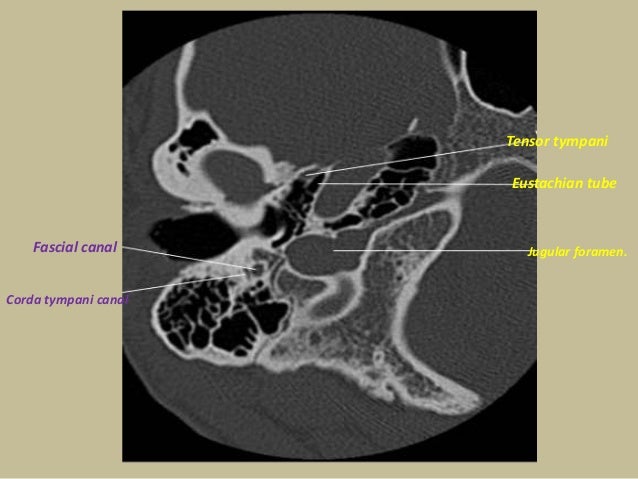

The tympanic segment of the chorda tympani cannot be seen as it traverse posteroanteriorly through the middle ear. The authors conducted a study to assess chorda tympani and trigeminal nerve function in these patients.

Middle ear structures, like incudostapedial joint, promontory or chorda tympani are invisible. A small cone of light can be seen in posterior quadrant. This is a picture of the child with normal tympanometry and tonal audiometry, without history of ear infections (fig.